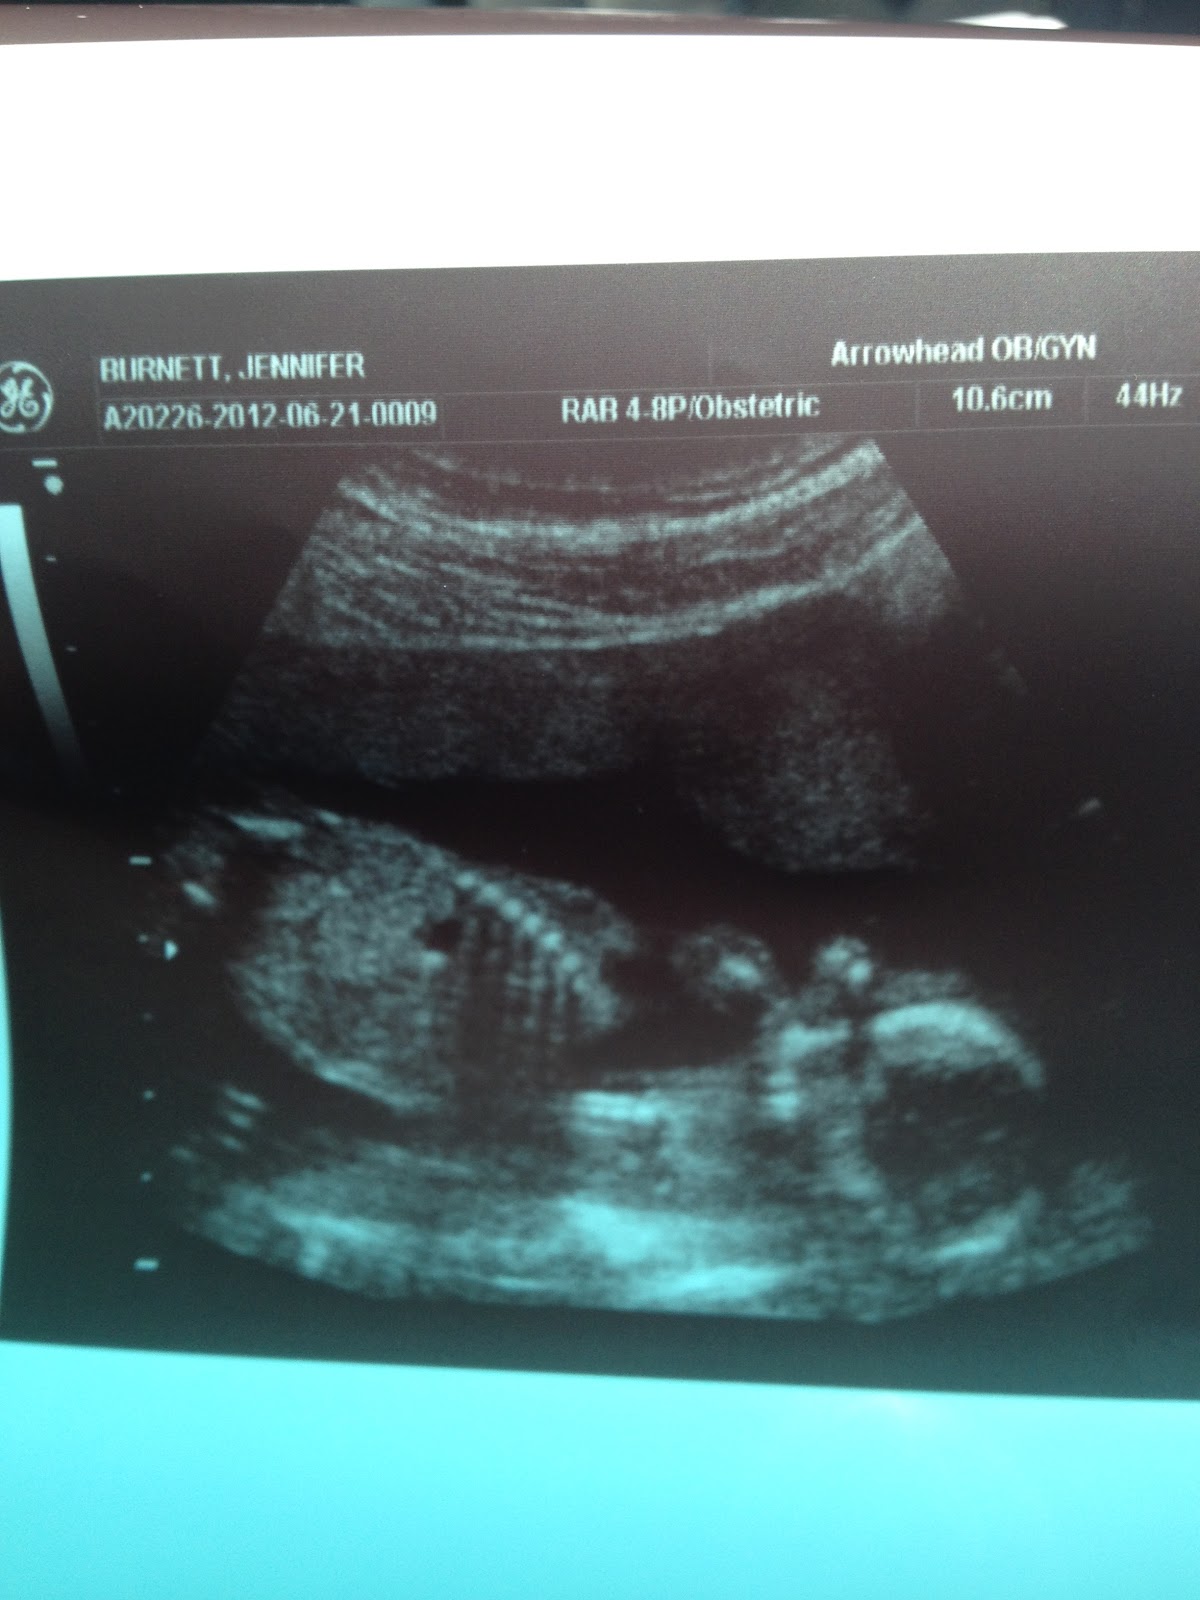

When we got home we had our first appointment with the new doctor. She is fantastic. I love that she was so willing to just talk to us and I felt as though she was listening. It was a nice change. We got to start the appointment with an ultrasound…

Baby looks great! Even though lil one didn’t want to show it’s face. Just like daddy “no pictures please”. We can’t wait until a month from now when we get to have the full anatomy scan and see all of the little body parts. We did get to check out one very important part at this appointment and we are thrilled to know the sex of our baby. I will post again in the next week or so to reveal that. But I want it to sink in first. We couldn’t be happier and once the triple screen blood test comes back with more positive healthy baby news I’ll be over the moon happy. Who knew that these little tests could be so stressful.